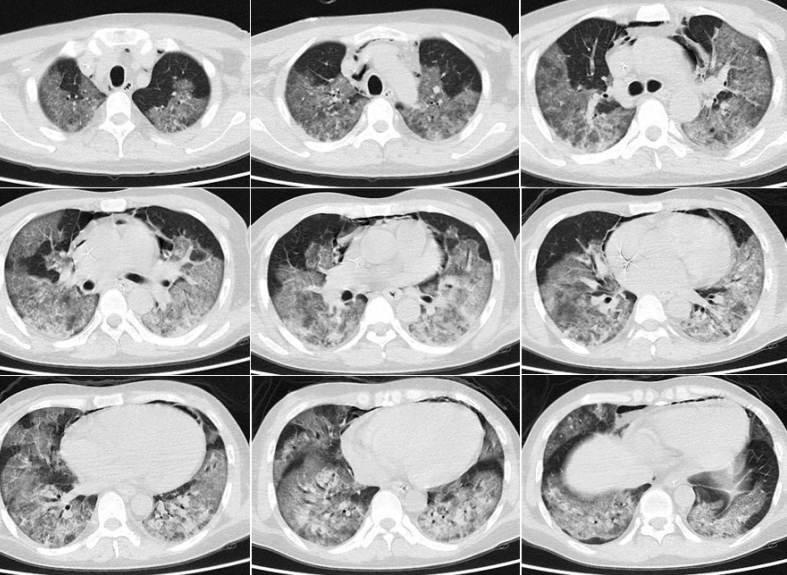

复查胸部CT

病变范围较前扩大,且出现气压伤、纵隔气肿。

图片